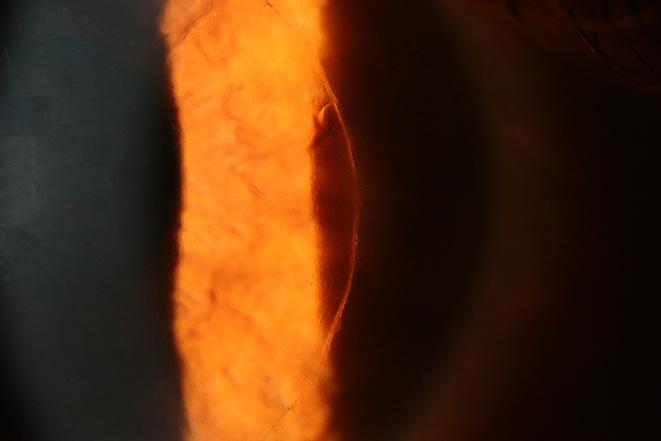

Snake Spectacle Vessel Permeability to Sodium Fluorescein

Python regius; ball python; ecdysis; fluorescein angiography; permeability; snake spectacle.

Objective

Assess vascular permeability of the snake spectacle to sodium fluorescein during resting and shedding phases of the ecdysis cycle.

Animal Studied

Ball python (Python regius).

Procedures

The snake was anesthetized, and spectral domain optic coherence tomography was performed prior to angiographic procedures. An electronically controlled digital single-lens reflex camera with a dual-head flash equipped with filters suitable for fluorescein angiography was used to make images. Sodium fluorescein (10%) solution was administered by intracardiac injection. Angiographic images were made as fluorescein traversed the vasculature of the iris and spectacle. Individually acquired photographic frames were assessed and sequenced into pseudo video image streams for further evaluation.

Conclusions

Fluorescein angiograms of the snake spectacle were readily obtained. Vascular permeability varied with the phase of ecdysis. Copious leakage of fluorescein occurred during the shedding phase. This angiographic method may provide diverse opportunities to investigate vascular aspects of snake spectacle ecdysis, dysecdysis, and the integument in general.